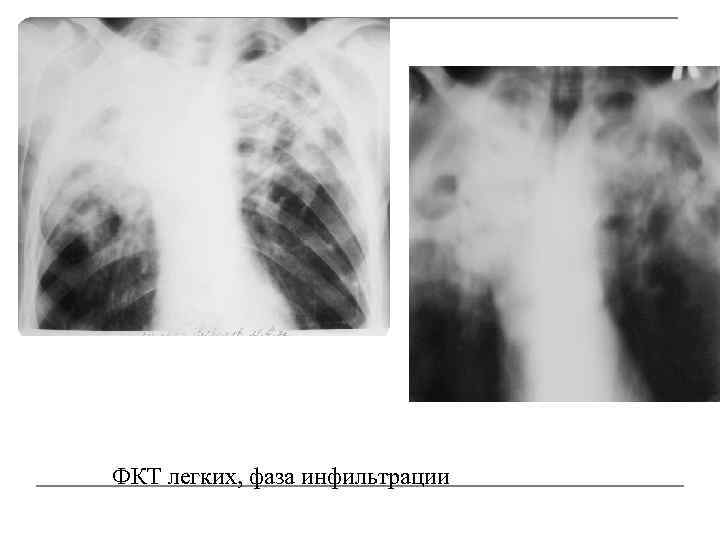

Симптомы и лечение инфильтративного туберкулеза легких

Раздел: Снимки-откровения